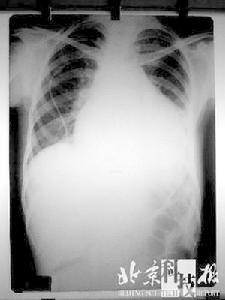

心臟·每3年進行一次肺部檢查。吸菸的人以及工作中與有毒物質打交道的人,請每年檢查一次。